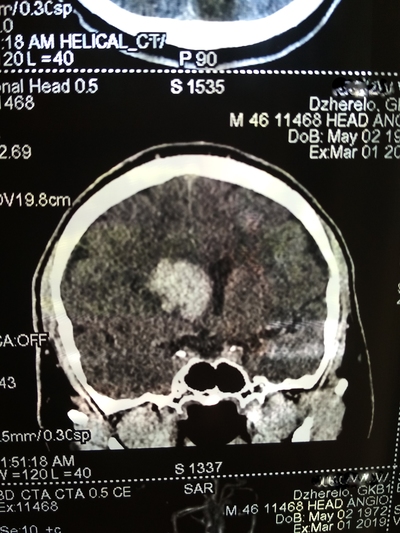

День не помню, возможно 1-2 марта, открываю глаза, а вокруг суета и непонятная обстановка. Осознаю что я а больнице, меня перетягивают с кровати на носилки и куда-то катят и тащат, укрыли сверху одеялом, внесли на улицу, очень холодно. Притащили (по другому не назовешь) меня на компьютерную томографию, перекинули с носилок на стол КТ, голову уложили в ячейку для головы и чем-то расклинили, чтобы не шевелился, больно капец. Я уже осознал что нахожусь в больнице, но что произошло не могу понять, да и думать мне было очень больно в голове.

Вернули меня в палату, перекинули на койку, и мои родные начали рассказывать, что 22 февраля мне стало плохо, качало, тошнило и рвало, жена подумала, что я выпил с друзьями в гараже. Потом вызвали скорую, которая померяла давление и там 290 на 160. Что то укололи. Потом возили в одну в больницу, они отказались принимать, повезли в другую. Вот так с 26 февраля я оказался в "еврейской", это у нас так называют гкб1. (городская клиническая больница № 1) По компьютерной томограмме врач определил геморрагический инсульт и аневризма, вот описание что это такое:

Пример аневризмы сосудов головного мозга

После КТ со мной общался врач, видя, что я уже в сознании, трогал руки ноги, просил потянуть рукой его руку, у меня плохо слушалась правая сторона тела.

Ещё врач сказал что желудочки головного мозга заполнились вытекшей кровью и они решают или вскрывать черепушку или медикаментозно лечить.

Вот тут я пересрал, совершенно не хотел проветривать бестолковку (но обрадовался когда на снимках всё таки обнаружили мозг 😁)